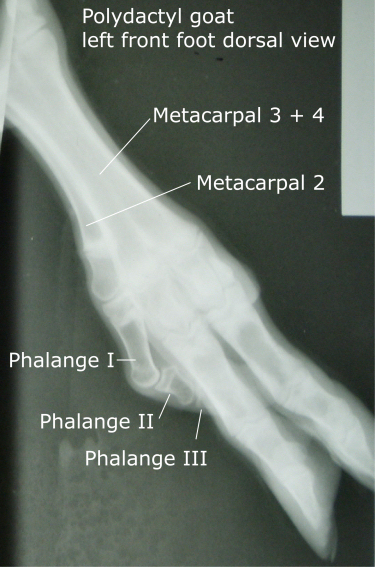

When the kid was about 4 months old I had the veterinarian take an xray of the leg. The radiographs revealed that the bones of the extra toe were complete all the way up to the knee. Unfortunately, the view did not include the carpal bones of the knee.

The illustration below helps explain what is seen in the xray. The bones of human hand are compared with the bones of the normal front leg of a goat and the bones of this polydactyl goat. The carpal bones which make up the human wrist are located in the area that we call the knee in the goat. The large bone just below the carpals is the fused third and fourth metacarpal bone. Goats do not have metacarpals 1, 2 and 5. The extra toe in the polydactyl goat is actually the second metacarpal bone with the additional phalanges 1, 2 and 3. The dewclaw is missing.